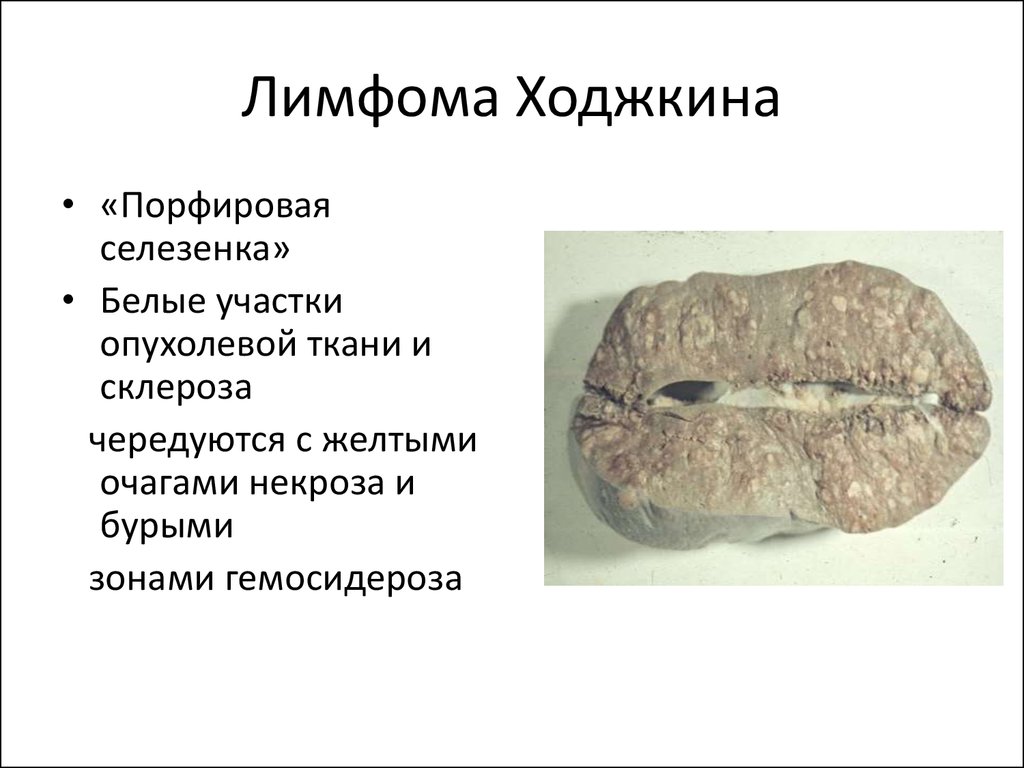

УЗИ лимфоузлов при лимфоме Ходжкина

Раздел: Образы вокруг